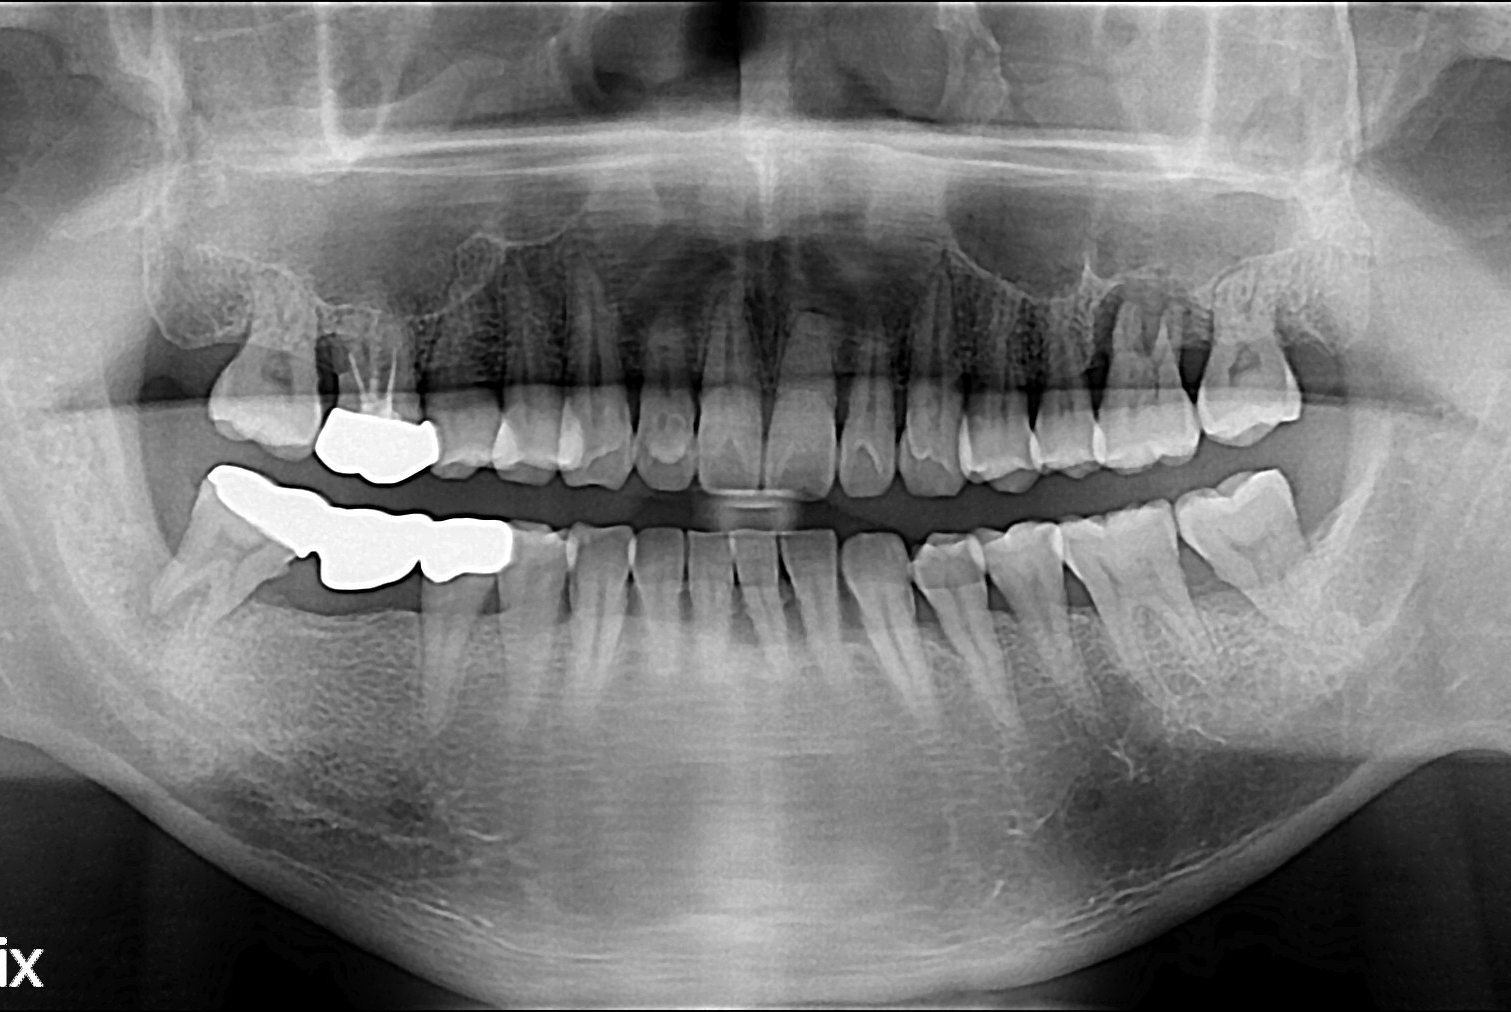

치료전 : 2019-09-20

세종치과는 많은 환자와 다양한 케이스를 바탕으로 항상 편안한 임플란트 수술을 제공하고자 노력하고,

오래동안 튼튼히 쓸 수 있는 임플란트 수술을 가장 큰 목표로 삼고 있습니다